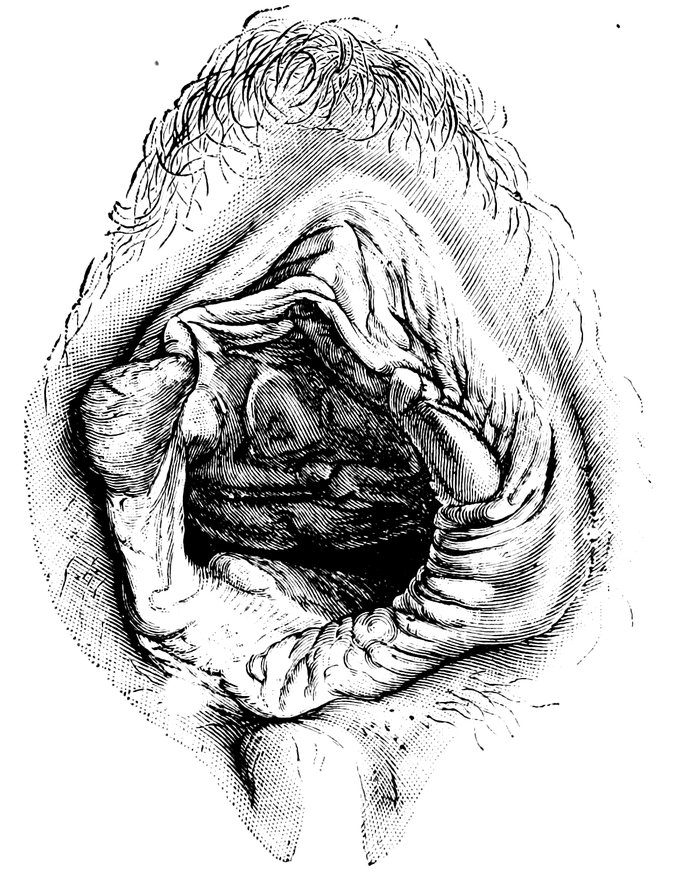

| 44. | Carunculæ Myrtiformes in a Primipara | 71 |

| 45. | Vaginal Inlet of a Multipara, without Carunculæ Myrtiformes. Slight Prolapse of Anterior and Posterior Vaginal Walls | 71 |

| 48. | The female pudendum, or vulva, with the labia majora | 204 |

| 49. | Vestibule of the vagina, with the labia minora or nymphæ, etc | 205 |